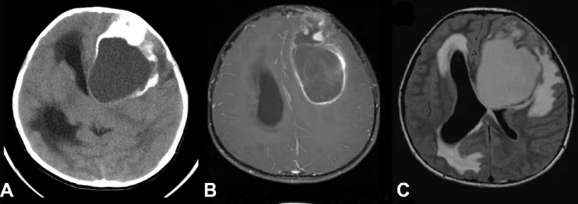

室管膜瘤(点击图片阅读)